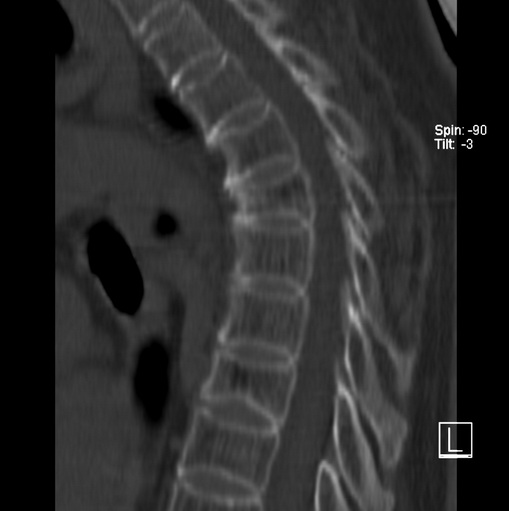

女、73、胸痛、胸闷3个月,无明显外伤病史,x线疑t4、t7陈旧压缩骨折,ct未经明显骨折,请问结论如何报?

老年女性病人,骨质稀疏,有些驼背,t4明显变扁,t7略变扁,椎体边缘无中断,骨小梁排列正常,无嵌插所致致密线。结合无明显外伤史,考虑老年骨质稀疏,慢性压缩改变,正如老年人骨质稀疏椎体呈双凹改变一样。我考虑报:老年骨质稀疏,t4、t7楔形变,脊柱曲度改变(驼背).敬请大家指教。

1)多个胸椎陈旧性压缩性骨折。2)胸椎普遍性骨质疏松。3)胸椎退行性改变。